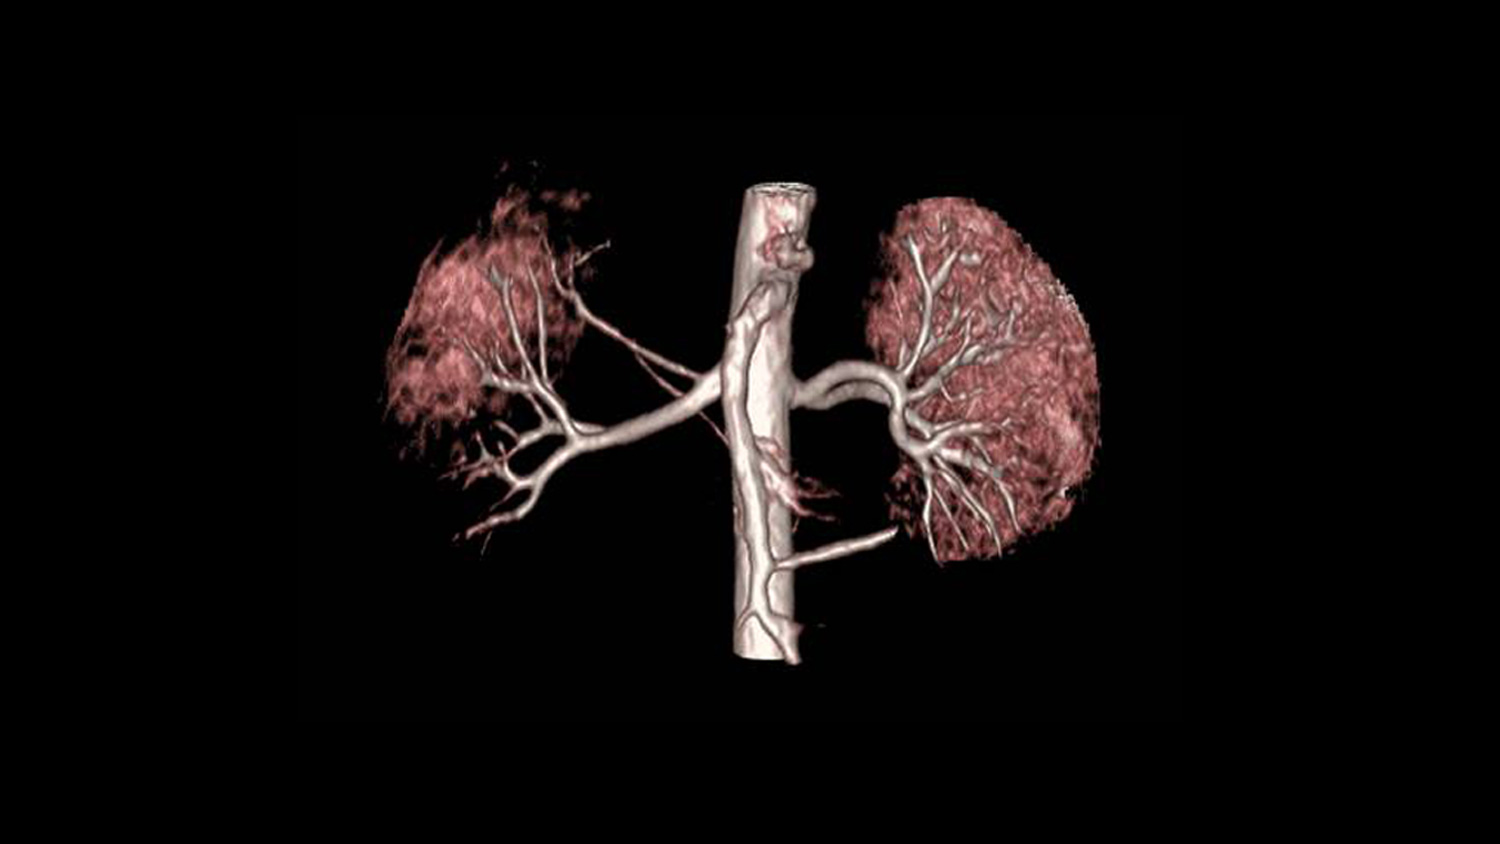

Ahora es posible realizar una angiografía a los pacientes con patologías renales sin necesidad de aplicar gadolinio y más importante sin sacrificar la calidad del estudio. La imagen es generada en alta definición (HD) y en reconstrucción 3D se puede ver a detalle de la anotomia renal del paciente. Con nuestra aplicación Inhance Suite 2.0 es posible visualizar el flujo arterial y venoso gracias a una avanzada gama de potentes y sólidas secuencias de pulso y sin necesidad de administrar contrastes de gadolinio.

Inhance es una técnica de angiografía sin realce de contraste por RM desarrollada para adquirir imágenes de las arterias y suprimir el tejido estacionario y el flujo venoso de fondo. Esta secuencia proporciona una excelente relación señal-ruido (SNR) y genera imágenes de sangre blanca. Se aplican pulsos selectivos de inversión sobre la región de interés para invertir el tejido arterial, venoso y estacionario. En el punto nulo de los tejidos de fondo, se aplica un pulso de excitación para generar la señal. El resultado neto es una imagen angiográfica con una excelente supresión de la señal de fondo y libre de contaminación venosa. La técnica selectiva de saturación espectral química (SPECIAL) le permite lograr una supresión uniforme de grasa, mientras que la compatibilidad con el gating respiratorio reduce los artefactos provocados por el movimiento respiratorio durante las exploraciones renales en respiración libre.

Nos permite adquirir imágenes angiográficas de las arterias cerebrales y renales con una excelente supresión de la señal de fondo en un reducido tiempo de exploración. Mediante la adquisición de imágenes volumétricas 3D de contraste de fase combinadas con imagen en paralelo, un eficaz muestreo del espacio k y la optimización de las secuencias de pulso, es capaz de registrar toda la anatomía neurovascular en aproximadamente cinco a seis minutos. Además, la supresión de la señal de fondo mejora gracias al diseño optimizado de la secuencia de pulso, lo que contribuye a una visualización detallada de las ramas de menor tamaño. La técnica de adquisición de señales sincronizada con el ciclo respiratorio (respiratory triggering) también es compatible con Inhance 3D Velocity, lo que permite llevar a cabo angiografías abdominales, especialmente de las arterias renales. El resultado es una productividad y calidad de imagen excepcionales.

Todas estas novedosas aplicaciones de Resonancia magnética nos permiten que sin realce de contraste se obtengan imágenes de las arterias periféricas. Está basada en secuencias 3D FSE con sincronismo cardiaco y adquiere dos ecos, uno en fase diastólica y otro en fase sistólica. La lentitud del flujo arterial durante la fase diastólica se traduce en arterias de sangre blanca en las imágenes diastólicas, mientras que el flujo arterial más rápido durante la fase sistólica resulta en arterias de sangre negra en las imágenes sistólicas. La sustracción de imágenes sistólicas de las imágenes diastólicas proporciona imágenes exclusivamente arteriales con una supresión excelente de la señal venosa y la señal de fondo. Adquisición entrelazada y con imagen en paralelo (ASSET) con una trayectoria optimizada del espacio k ayuda a reducir el registro de movimiento y a mejorar la visualización de los vasos respectivamente. Además, la adquisición de imágenes con transformada de Fourier parcial y de planos coronales permite reducir considerablemente el tiempo de exploración.

“Inhance Inflow IR proporciona imágenes exquisitas de la vasculatura renal, capaces de mostrar con precisión los vasos accesorios más pequeños y distales imposibles de visualizar en las RM con realce de contraste. Es la técnica de RM que estábamos esperando”